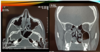

Q

A

Posterior porque no hay crista gali, etmoides posterior

Afectado seno maxilar izq, derecho. Imagen ocupación 50%, homogéneo, de superficie convexa. Mucocele porque es convexo. Sinusitis maxilar BL. Hay sinusitis etmpdodal. Para que etmpides esté sano debemos de ver trabeculas del hueso super flaquitas.

Si se ve engrosado es sinusitis etmoidal

Sinusitis maxiloetmoidal bl con posible presencia de mucocele o quiste de retención de lado derecho.